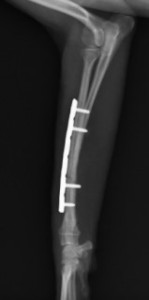

手術前

手術後

ロッキングプレートで整復しました。